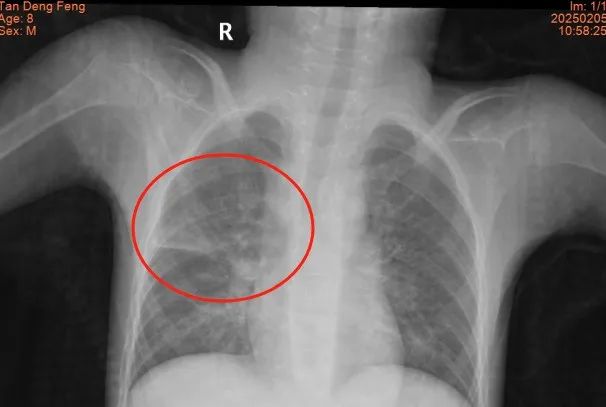

患儿小小,患有脑瘫与药物难治性癫痫,重度营养不良,7岁体重仅10公斤,因长期卧床导致肺部感染并发肺脓肿,入院时情况极为复杂,胸部CT显示肺脓肿、肺炎合并胸腔积液,高热不退、呼吸困难,惊厥频发,治疗难度极大,家属几近绝望,甚至动过放弃治疗的念头。